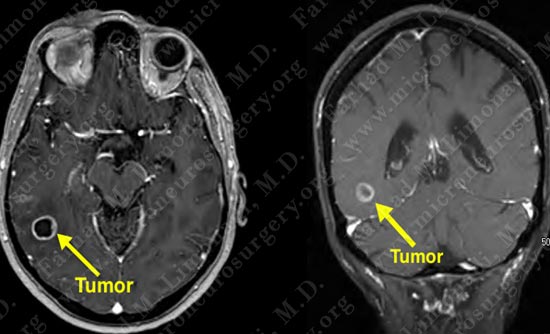

Imaging

MRI scan of her brain shows a right posterior temporal contrast enhancing mass (tumor). The tumor is marked in the left side of the slides (right side of patient's brain).